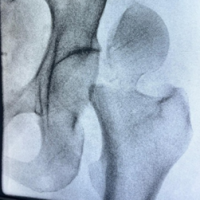

Rehabilitation program included touch weight bearing on the right lower limb for 6 weeks along with leg elevation and active movements of the hip. Hip abductor strengthening, static and dynamic quadricep strengthening exercises. Post-operatively, at 6 weeks, the patient had a good range of movements of the hip, was able to fully weight bear and walk independently without assistance. At 3 months post-operatively, the patient reported significant improvement in pain and function. He was walking independently with a normal gait, the Trendelenburg test was negative, and hip range of motion was full and painless (110° of hip flexion and normal rotations). The Harris hip score improved from 36 pre-operatively to 89 at follow-up. Follow-up radiograph at 1 year showed good joint space, congruent articular surfaces, and no evidence of AVN of the femoral head (Fig. 6).

Figure 6: Anteroposterior and lateral radiographs of the right hip at 1-year follow-up.